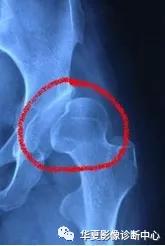

平片常规摄双髋正位和蛙式位片,典型表现包括:

①股骨头向外上移位;

②股骨头骨骺发育小、不规整,或出现延迟;

③髋臼顶发育不良呈斜坡状,髋臼角加大,可达50° - 60°;

④患侧股骨发育较细小,股骨颈短缩。

⑤骨盆:单侧脱位骨盆倾斜,双侧脱位骨盆较垂直、前倾。

⑥包绕股骨头的半弧形关节囊其上缘与髋臼顶不相接,其上方可见三角形透亮区。